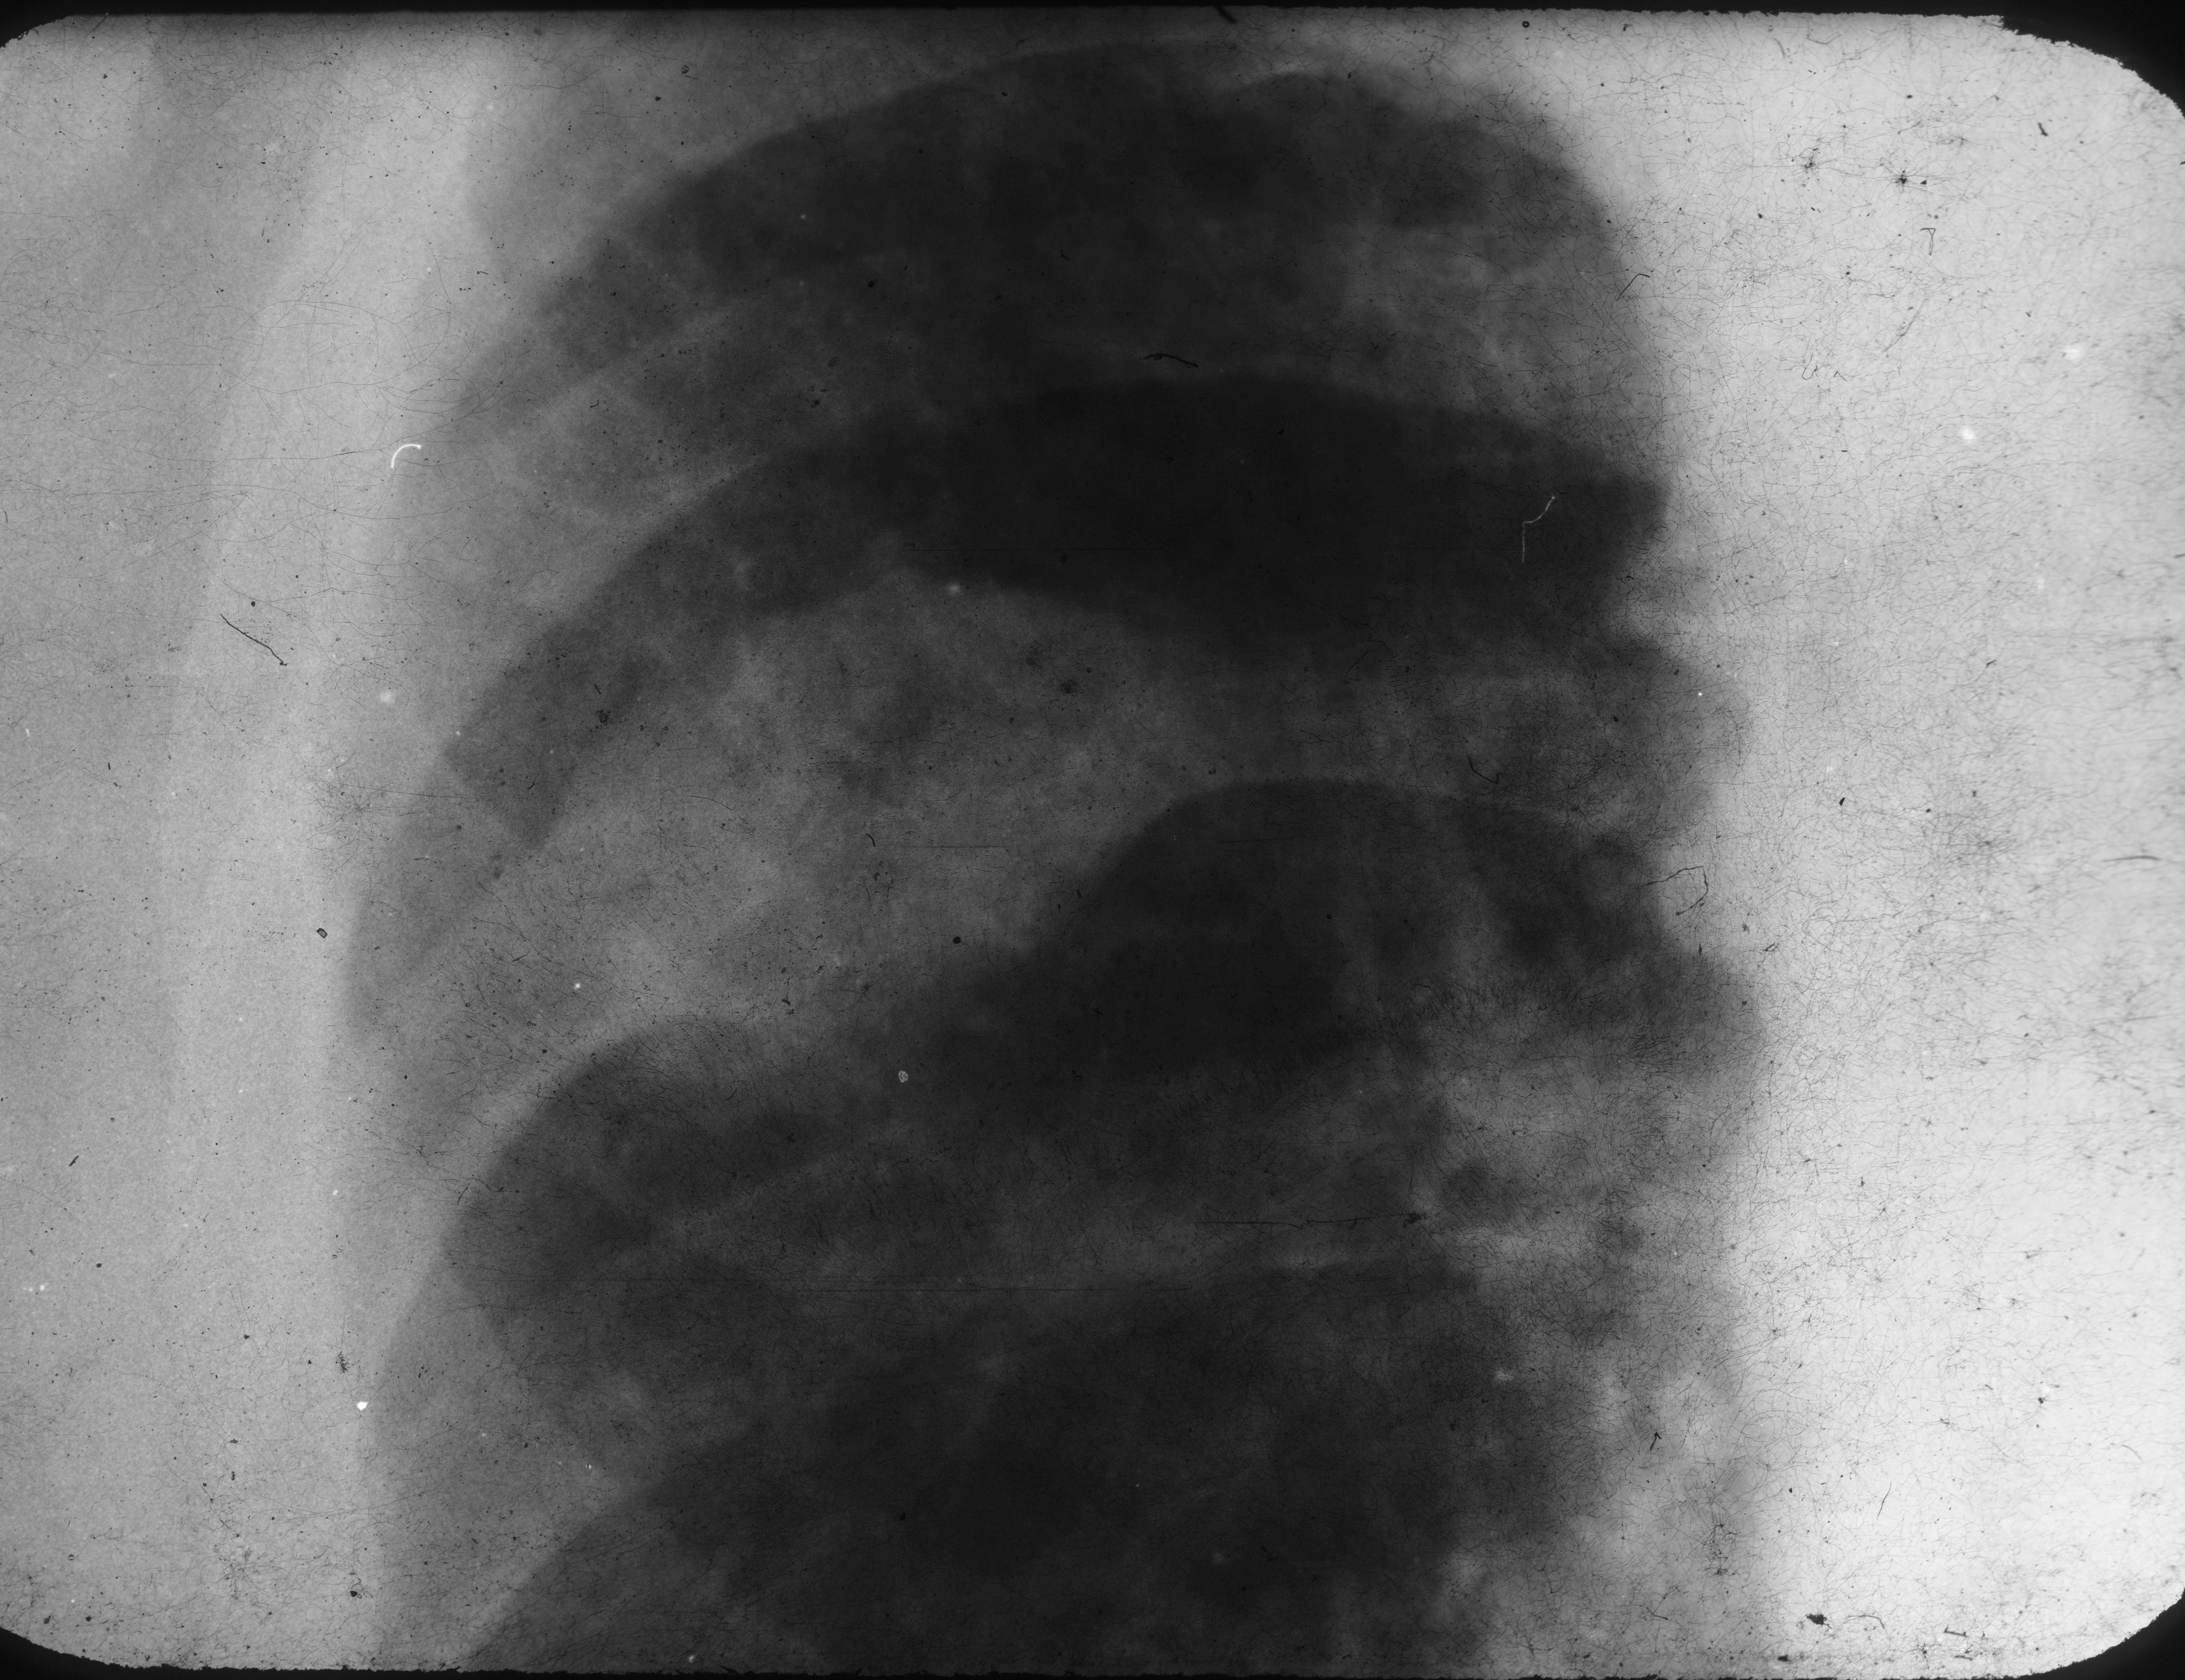

Ground glass appearance in an expanded lesion is characteristic (Figure 9).

Figure 9: FD – Right 5th rib shows localized expansion with new bone formation.